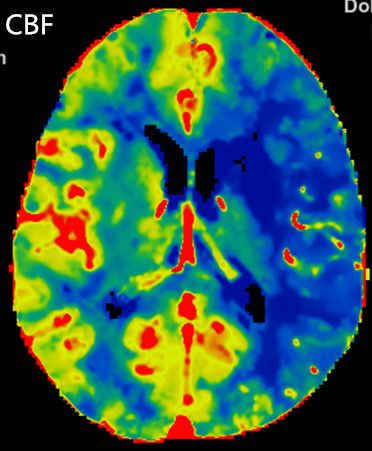

多模式CT影像提示:左侧大脑中动脉M1段闭塞,存在CBF-CBV不匹配。

术前影像

向右滑动查看更多

图1急诊颅脑CT

图3 CTP存在CBF-CBV不匹配

1.术前诊断:急性脑梗死,左侧大脑中动脉闭塞。

2.手术指征:患者应用阿替普酶溶栓后症状仍持续加重,CTA示左侧大脑中动脉闭塞。CTP存在CBF-CBV不匹配,有介入治疗指征。